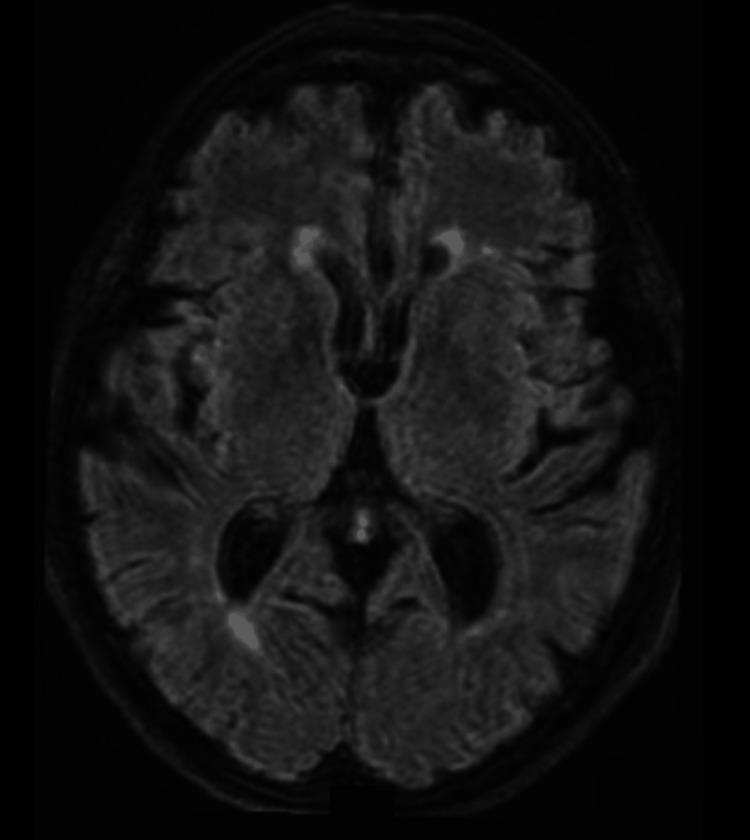

Limbic encephalitis is a relatively rare autoimmune neurological disorder, typically diagnosed based on clinical symptoms lasting less than three months, including seizures, memory deficits, psychiatric symptoms, bilateral mesial temporal lesions on MRI, inflammatory cerebrospinal fluid, and epileptiform activity on electroencephalogram (EEG). We report the case of a female patient who presented with an inaugural epileptic seizure, for which MRI, lumbar puncture, and cerebral positron emission tomography (PET) scan showed no pathological findings. The patient re-presented to the emergency department one month later with recurrent seizures. A subsequent PET scan revealed the emergence of a right mesial temporal lesion, and a hypermetabolic pulmonary lesion was identified, which was later diagnosed as small-cell lung carcinoma on histopathology. The patient showed favorable clinical improvement under Solu-Medrol treatment, and a follow-up imaging performed several months later showed complete resolution of the hypermetabolic cerebral lesion after chemotherapy. This case highlights an unprecedented early stage of limbic encephalitis, characterized by an initial absence of inflammation, suggesting that this might represent a nascent phase of the disease, which could be crucial for future management of similar cases.

边缘叶脑炎是一种相对罕见的自身免疫性神经系统疾病,通常根据持续时间少于三个月的临床症状进行诊断,这些症状包括癫痫发作、记忆缺陷、精神症状、磁共振成像(MRI)显示双侧内侧颞叶病变、炎性脑脊液以及脑电图(EEG)上的癫痫样活动。我们报告了一例女性患者,其首发癫痫发作时,MRI、腰椎穿刺和脑正电子发射断层扫描(PET)均未发现病理结果。一个月后,该患者因癫痫复发再次就诊于急诊科。随后的PET扫描显示右侧内侧颞叶出现病变,同时发现一个代谢亢进的肺部病变,组织病理学检查后来诊断为小细胞肺癌。该患者在接受甲泼尼龙治疗后临床症状明显改善,数月后进行的随访成像显示化疗后代谢亢进的脑病变完全消失。该病例突出了边缘叶脑炎前所未有的早期阶段,其特征是最初不存在炎症,这表明这可能代表疾病的初始阶段,这对未来类似病例的管理可能至关重要。